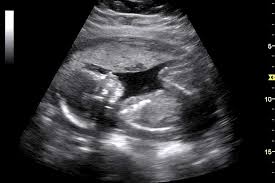

1. ضربان قلب بالاتر جنین در دوران بارداری